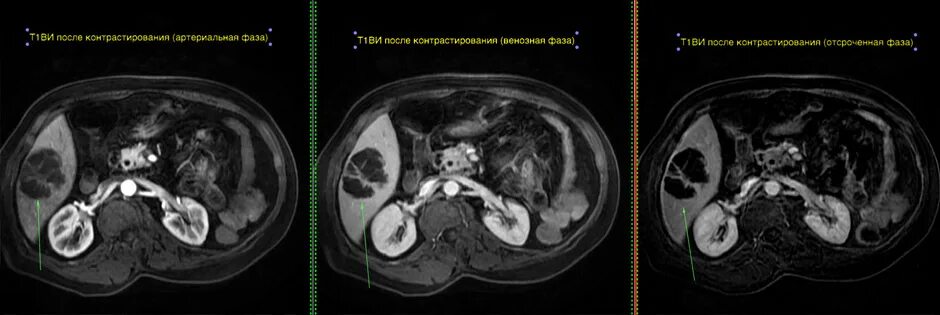

Мскт болюсное контрастирование. болюсное контрастирование при кт. кт с внутривенным болюсным контрастированием. болюсное контрастное усиление при кт.Компьютерная томография с болюсным контрастированием. кт с болюсным контрастированием что это. мскт болюсное контрастирование. спиральная компьютерная томография с болюсным контрастированием.Отечная форма панкреатита кт. кт признаки острого панкреатита. острый панкреатит кт с контрастированием. кт картина панкреонекроза.Томография с болюсным контрастированиемБолюсное контрастирование при кт брюшной полости. хемодектома забрюшинного пространства. кт с контрастом брюшной полости с болюсным контрастированием. эхинококкоз кт с контрастированием.Фазы контрастирования печени мрт. динамическое контрастирование печени мрт. фазы контрастирования при кт. кт с контрастом брюшной полости с болюсным контрастированием.Компьютерная томография с болюсным контрастированием. кт с болюсным контрастированием что это. кт с внутривенным болюсным контрастированием. болюсное контрастное усиление.Кт с болюсным контрастированием что это. компьютерная томография с болюсным контрастированием. методика болюсного контрастирования. кт обп с болюсным контрастированием.Компьютерная томография с болюсным контрастированием. кт перфузия головного мозга. методика болюсного контрастирования.Томография с болюсным контрастированиемТомография с болюсным контрастированиемКт брюшной полости аорты с контрастированием. кт почек с болюсным контрастированием. контрастирование при кт. контрастное усиление при кт.Томография с болюсным контрастированиемТомография с болюсным контрастированиемТомография с болюсным контрастированиемТомография с болюсным контрастированиемОментит кт. компьютерная томография пжж. кт с болюсным контрастированием панкреатит.Кт с болюсным контрастированием что это. компьютерная томография с болюсным контрастированием. кт брюшной полости презентация.Кт огк с контрастированием. скт огу с контрастированием. кт огк, обп с контрастированием. кт с внутривенным контрастированием.Кт с болюсным контрастированием и пэт кт. контрастное усиление при кт обп. кт с болюсным контрастированием что это.Томография с болюсным контрастированиемТомография с болюсным контрастированиемТомография с болюсным контрастированиемТомография с болюсным контрастированиемТомография с болюсным контрастированиемТомография с болюсным контрастированиемТомография с болюсным контрастированиемТомография с болюсным контрастированиемТомография с болюсным контрастированиемТомография с болюсным контрастированиемТомография с болюсным контрастированиемТомограмма брюшной полости кт. кт обп норма. кт брюшной полости и забрюшинного пространства. кт обп с контрастированием норма.Томография с болюсным контрастированиемКт с контрастированием почек онкология. кт ангиография почечных артерий. кт почек с контрастированием норма.Спиральный компьютерный томограф с болюсом. компьютерная томография с болюсным контрастированием. кт с внутривенным болюсным контрастированием.Кт головного мозга с контрастированием. мрт головного мозга с контрастом. кт с контрастом.Мрт обп с контрастом. мрт исследование с контрастированием. кт с контрастированием. кт брюшной полости с контрастом.Томография с болюсным контрастированиемКт с контрастированием брюшной полости контрастированием органов. кт почек с болюсным контрастированием. кт обп с болюсным контрастированием. томограмма брюшной полости кт.Кт ангиограмма. кт ангиография с контрастированием. кт-ангиография артерий нижних конечностей.